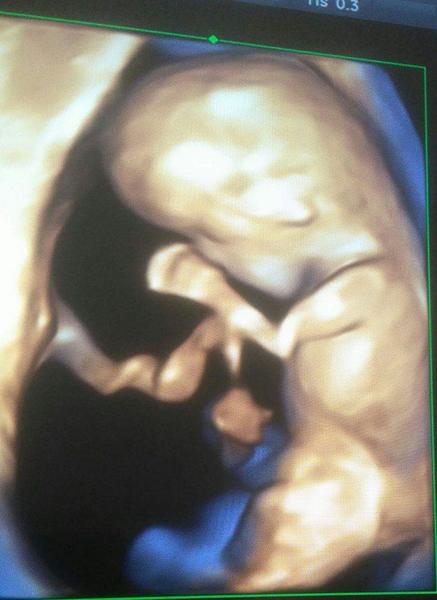

@candies moja gynekologička nie tá má dosť slabé sono ale Dr Višňovský on nás lieči tak on nám aj v 12tt robil to 3D toto je fotka z 12tt 😍